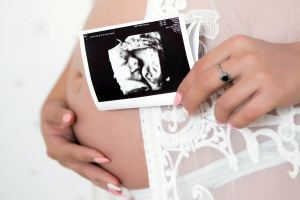

Prin serviciile de obstetrică oferite de clinica noastră ne ocupăm de îngrijirea femeii însărcinate și a fătului. Aceasta înseamnă perioada preconcepției și derularea sarcinii în ansamblu. Apoi, travaliul și nașterea pentru a culmina cu perioada post-natală.

La Ambulator Clinic Europa Timișoara depistăm, diagnosticăm și tratăm afecțiunile aparatului reproductiv feminin. Depunem eforturi pentru recuperarea genitală după tratamentele medicale. Și de fapt întreaga problematică de servicii și tratamente ginecologice.